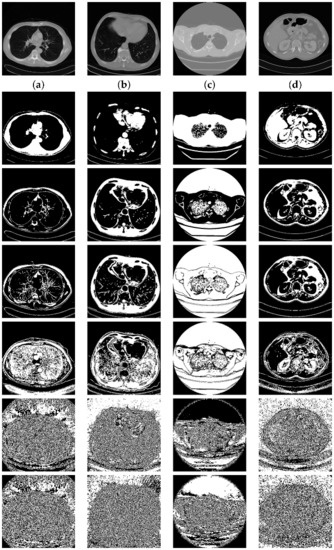

Figure 7.

Bit planes extracted from the medical images (Row 1: original images; (a) medical image-1; (b) medical image-2; (c) medical image-3; (d) medical image-4. Row 2: plane 7; row 3: plane 6; row 4: plane 5; row 5: plane 4; row 6: plane 1; Row 7: Plane 0).